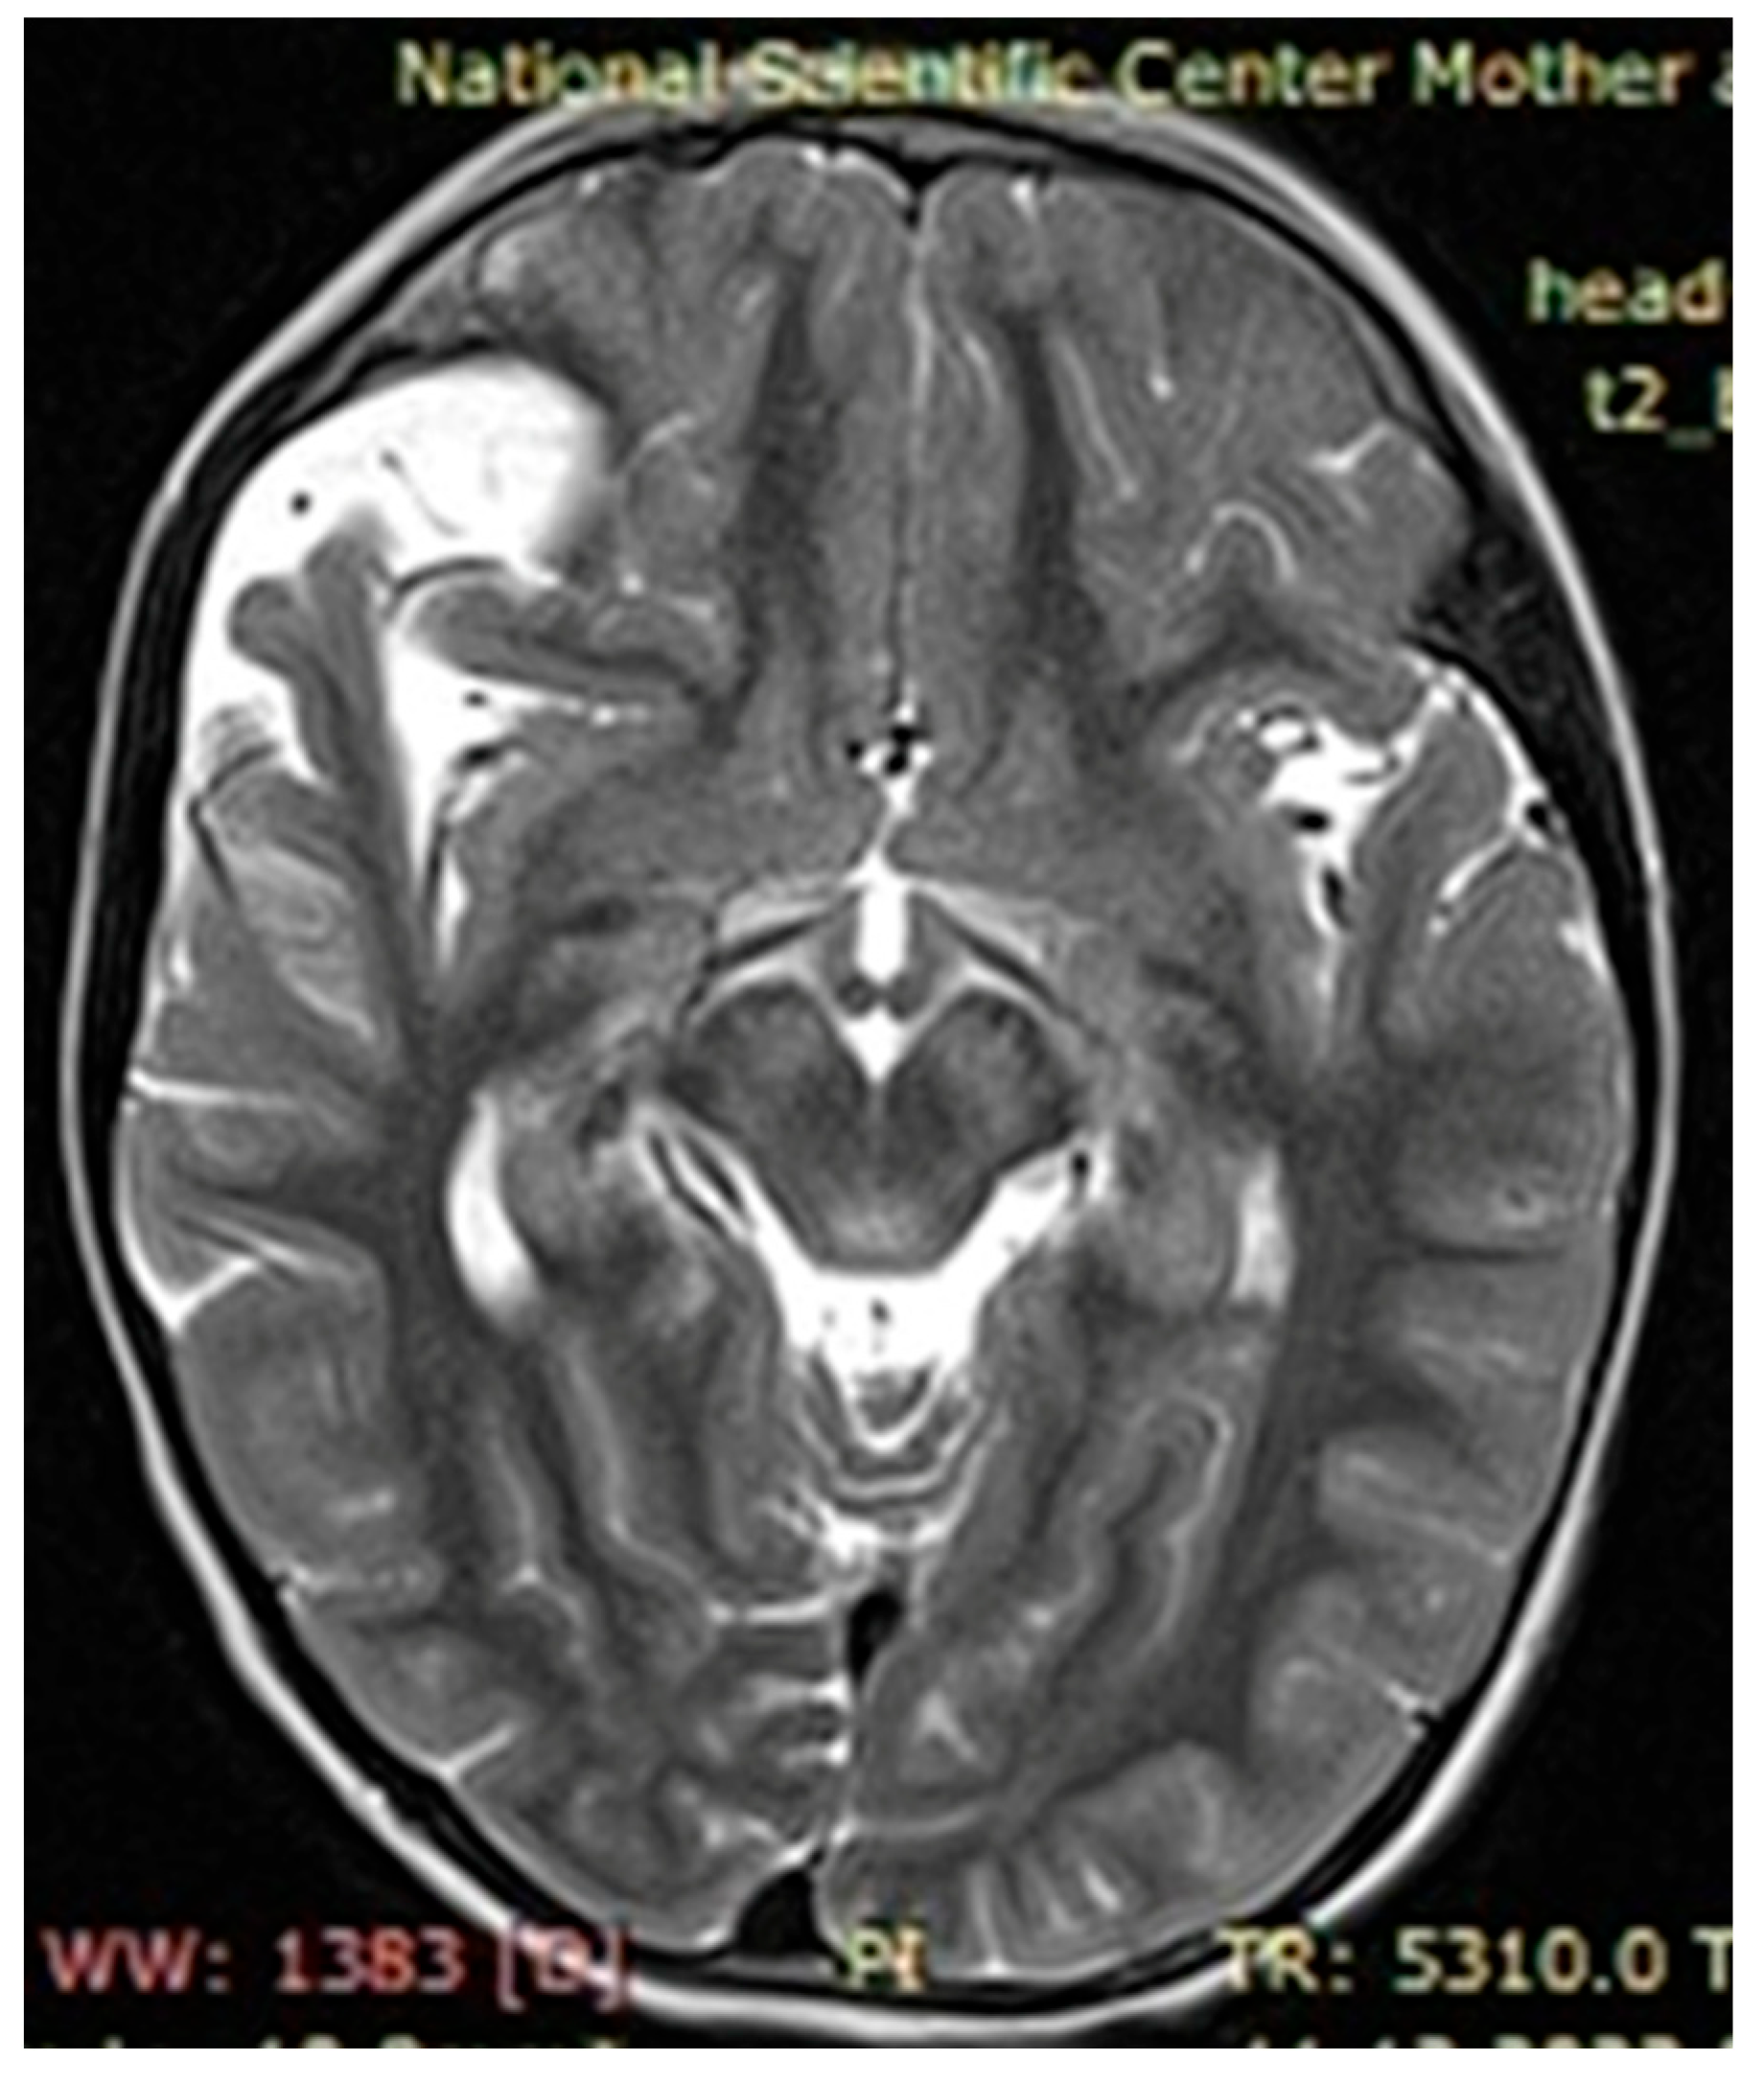

The observed café au lait macules originated in the early childhood of our patients and in most cases grew as they approached adolescence. Around 60% of patients with neurofibromatosis had two, simpler neurofibromas, characterized by nerve hypertrophy, which in turn caused displacement of adjacent tissues, organs, and bones if located next to the pelvis and/or spinal cord. There were several patients presenting with severe cases of scoliosis, lordosis, and torsion of the rib cage due to ongoing growth of neurofibromas, identified via MRI as focal areas of increased signal intensity, with space-occupying lesions verified on the T2-MRI STIR (Short Tau Inversion Recovery) regime as plexiform neurofibromas.

Upon further growth of neural tissues, patients presented with plexiform neurofibromas, located around the eye tract, neck, spinal cord, and groin (examples presented in Figure 3, Figure 4 and Figure 5). A total of 14 patients presented with optic nerve and optic tract glioma as well as retinopathies, retinal angiopathies, declined vision, astigmatism, and other eye pathologies. Many patients complained that eye plexiform neurofibroma occluded their vision, causing gradual vision loss due to lack of accommodation and increased tissue growth.

Figure 3. Case 1, clinical diagnosis of a 14-year-old girl: neurofibromatosis 1, full facial plexiform neurofibroma, especially eye lids, forehead, and the orbits of both eyes, with compression of the eyeballs. With the deletion of the NF1 gene Chr17, deletions NM_000267.4:c.3843delC.

Figure 4. Case 2, clinical diagnosis of a 12-year-old boy: neurofibromatosis type 1, plexiform neurofibroma of the left periorbital region, mild truncal ataxia, and mild dysmetria. With single nucleotide replacement variant NF1 Chr17 NM_000267.4:c.5792G>A.